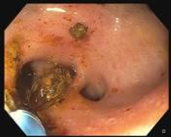

Cholangiogram through choledochoduodenostomy revealed multiple filling defects located mostly in liver segment IV. Extraction of many stones was achieved using a SpyGlass™ Retrieval Basket through 18 Fr gastroscope. Segment IV takeoff was dilated to 8 mm using a through the scope balloon. Cholangioscopy using SpyScope™ DS through therapeutic gastroscope with cap was performed revealing many remaining intraductal stones (Figure 3). Extraction of stones with SpyGlass Retrieval Basket enabled complete clearance of segment IV stones (Figure 4, 5).